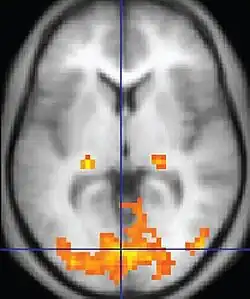

Exames de imagem apontam evidências de alterações estruturais em determinadas regiões do cérebro, o que comprova o forte fator genético. Tais formações se dão logo após a concepção, ainda em estado embrionário, e são características que quase sempre podem observadas também nos pais ou em um deles, caracterizando o que se chama de Fenótipo Ampliado do Autismo (FAA), que é quando o indivíduo não tem a síndrome completa, mas possui alguns traços. Irmãos de crianças com a Síndrome de Asperger, muitas vezes, também apresentam traços ou condições afins, mais uma vez reforçando a ligação genética do quadro.